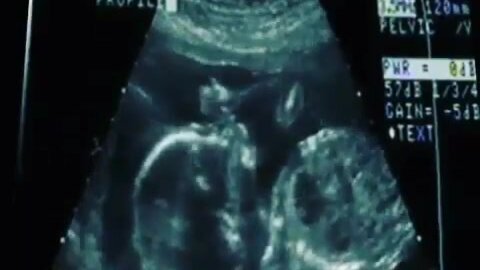

Так выглядит сосательный рефлекс у плода